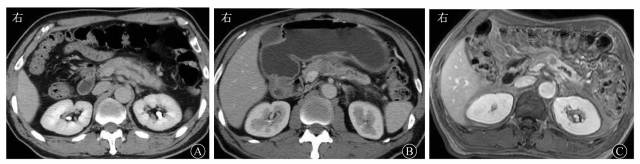

文献报道MSCT检测胰腺癌的敏感度可达90%以上。胰腺癌通常在CT图像上表现为边界不清的实性肿块,相对正常胰腺实质略微低密度。胰腺癌合并急性胰腺炎的直接征象是胰腺轮廓扭曲,异常增多的软组织肿块突出于胰腺轮廓外,侵入相邻器官和(或)血管结构,增强呈轻度强化(图1A、图1B);如果同时发现淋巴结肿大或肝转移,则可以确立诊断。

图158岁男性胰体导管腺癌合并急性胰腺炎患者的影像学表现 A 计算机断层扫描增强门静脉期图像示胰腺肿胀,胰体尾部胰管轻度扩张,胰周少许渗出 B 2个月后计算机断层扫描增强门静脉期图像示胰腺体积减小,周围渗出减少,胰体见稍弱强化结节,远端胰管扩张C 2个月后磁共振增强门静脉期图像示胰腺体部弱强化结节,显示更清晰,远端胰腺体尾部强化明显,胰管扩张,术后病理证实为胰体导管腺癌,阻塞胰管引起胰腺炎

在慢性胰腺炎中可见到胰管穿过肿块,在胰腺癌中胰管表现为不规则狭窄或完全阻塞。DWI和动态增强MRI能够区分肿瘤组织和水肿性纤维化。多b值体素内非相干运动(intravoxel incoherent motion,IVIM)方法已经应用于胰腺成像,并且已有鉴别胰腺癌和正常胰腺的有价值的研究结果。动态增强MRI提高了胰腺和肿瘤的信号强度差异,有利于小胰腺癌的检出(图1C),也可以用于区分胰腺癌与由慢性胰腺炎引起的局部肿块,有利于检出长期慢性胰腺炎癌变或合并的胰腺癌。